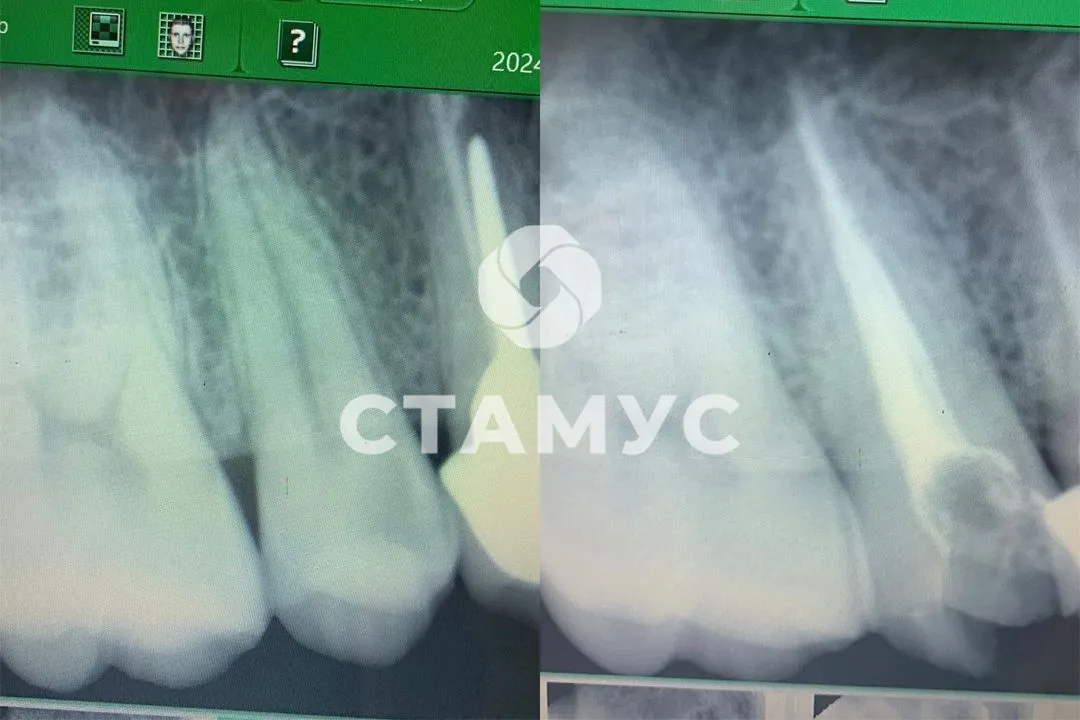

Пациен 18 лет, жалобы на разрушенность зубов.

На мезио-дистальной поверхности 43-42 з кариозные полости в пределах дентина.

Под инфилтрационной анестезией проведена изоляция системой коффердам, препарирование кариозных полостей, медикаментозная обработка, постановка пломбы.